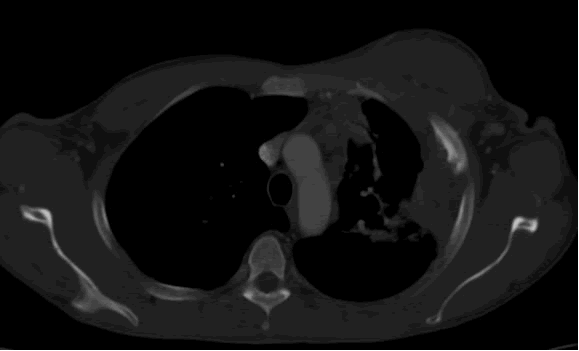

PA and lateral chest film revealed patchy consolidation of the left lung with a large pleural-based mass, left apical pleural thickening, and right upper lobe scarring (Figure 1). Helical CT scan of the chest, abdomen, and pelvis with contrast demonstrates a large, 10.8 x 4.1 cm left pleural-based mass extending into the chest wall and left breast (Figure 2). There was periosteal thickening and irregularity of adjacent ribs. Multiple enlarged mediastinal, left hilar, and supraclavicular nodes were noted, the largest 1.5 x 2.6 cm in the AP window or station five region. There was patchy consolidation of the left and right upper lobes. An MRI of the thorax with contrast was obtained and confirmed the presence of left supraclavicular adenopathy and an enhancing mass with extension into the chest wall involving the ribs, infiltration of the pectoralis muscle, and extension into the left lung parenchyma. The main differential diagnoses at this time were neoplasm (sarcoma, advanced lung cancer, mesothelioma, lymphoma, osteosarcoma).